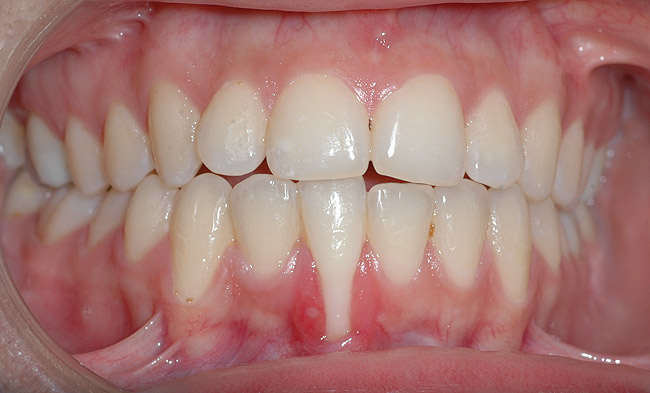

CASE 1 Fig 2. Pre-treatment clinical view of a 28-year-old patient with Miller Class I recession of the lower left central incisor treated with conservative SPT.

Figure 2

Fig 3. Two-year follow-up of same patient shows spontaneous root coverage.

Figure 3

When the tooth is properly aligned within the arch, treatment is managed with reference to Miller’s classification.7 Because most post-orthodontic GR cases are classified as Miller Class I and II defects, the authors focus on the management of these two classes only, and within the scope of this article, Miller Class III and IV defects are not addressed. Surgical root coverage of both Miller Class I and II defects is one treatment choice. However, in Miller Class I cases, a conservative approach can be considered, as well. Such an approach consists of supportive periodontal treatment (SPT)—professional periodic deposit removal every 2 to 3 months during a 1- to 2-year period. The authors’ clinical experience shows that spontaneous root coverage may occur following this conservative approach, particularly in young patients (Figure 2 and Figure 3). Similar results have been reported in a 3-year prospective study in which recession defects healed spontaneously following improvement in oral hygiene standards in children.30 In cases in which no root coverage is observed at the end of the follow-up period, surgical root coverage can be considered.